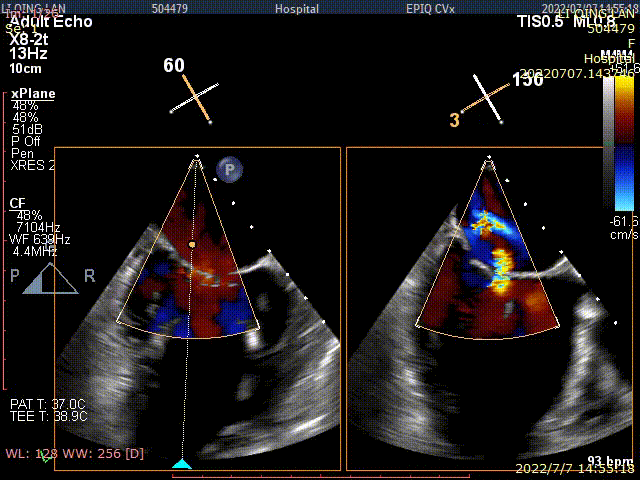

术后TEE显示,二尖瓣双孔化形成,反流明显减少